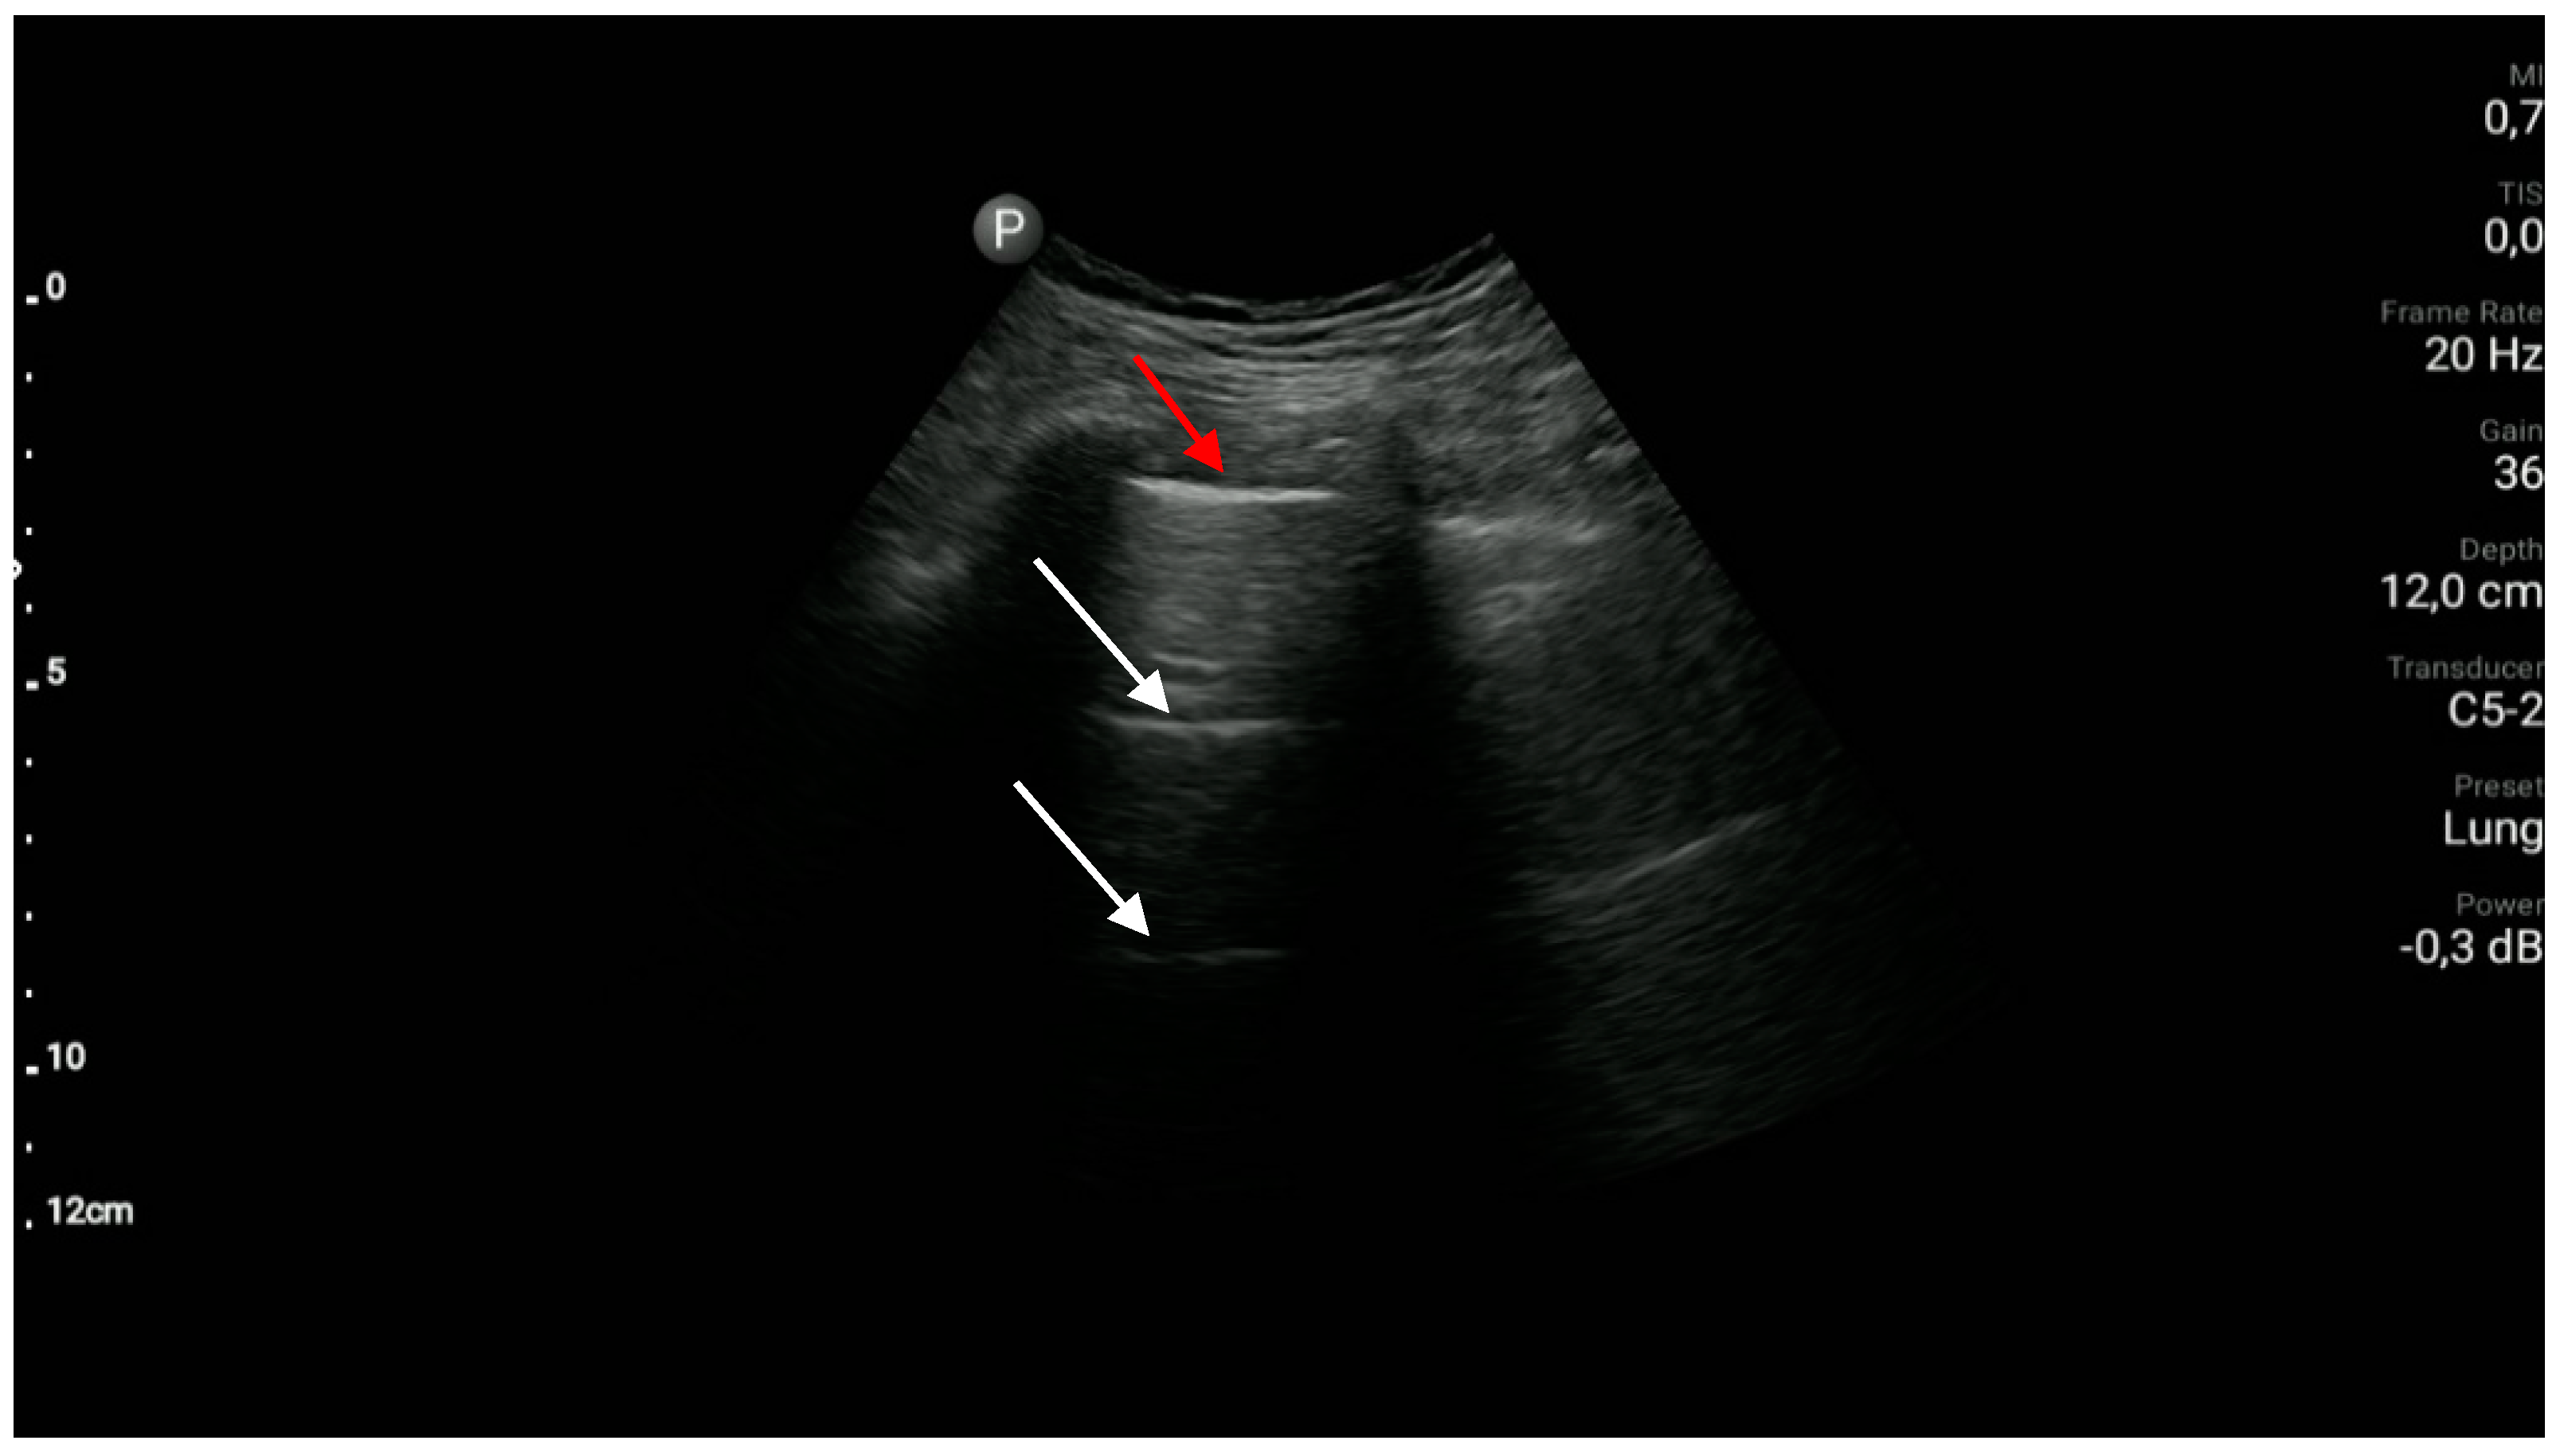

- The sonographic features of pneumothorax are as follows: absence of lung sliding, absence of vertical reverberation artifacts, absence of the lung pulse sign, and the presence of the lung point. (A1)

- The presence of lung sliding and/or vertical reverberation artifacts rising from the pleural line and/or the lung pulse excludes pneumothorax. (A1)

- The lung point is the border between the pocket of pleural air and the normal pleural cavity; this sign can be visualized in the B or M-mode.

- The lung pulse is the pulse of the lung resulting from cardiac motion transferred to the lung; the lung pulse is best visualized in the M-mode and/or power/color Doppler options.